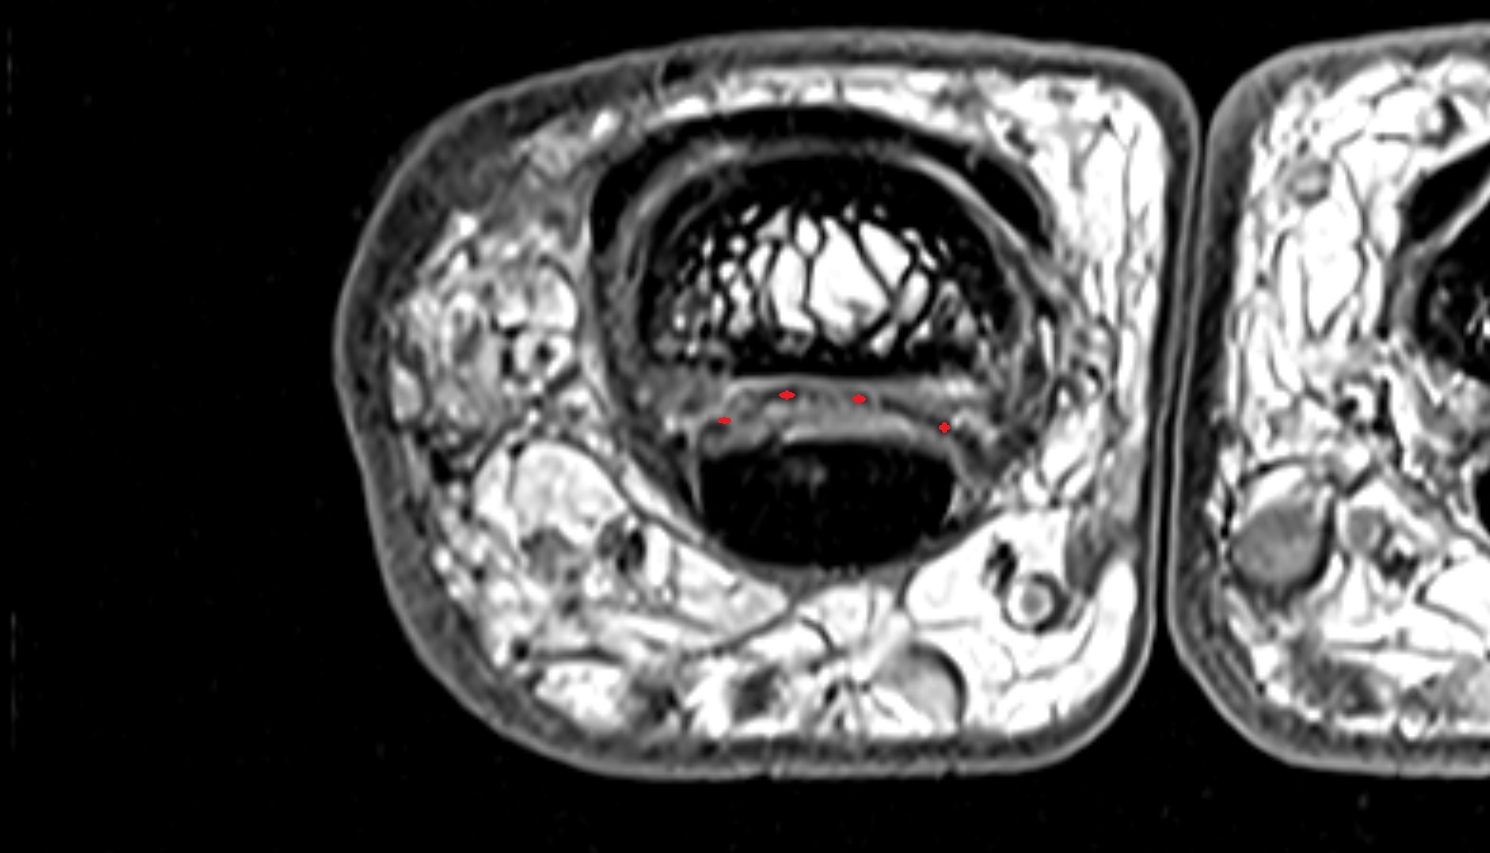

- Peripheral zone of prostate

- Anterior Fibromuscular Stroma of prostate

- Central zone of prostate

- Transitional zone of prostate